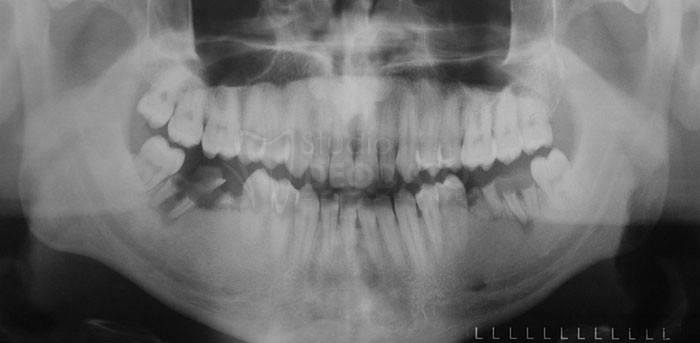

Ortopantomografia o radiografia panoramica o Rx-OPT

È l’elemento diagnostico più utilizzato oggi in odontoiatria.

L’OPT fornisce una immagine completa delle arcate dentarie e delle strutture ossee da cui sono sostenute. Anche se ben realizzata, essa non riesce a fornire una rappresentazione dimensionale accurata potendo dare alcune volte una deformazione del 30% quindi non in grado di valutare la giusta altezza ossea.

Comunque questo esame ci dà una valutazione d’insieme del caso, la posizione e l’ampiezza dei seni paranasali, il decorso del nervo alveolare inferiore, la posizione dei forami mentonieri e sottorbitari e l’eventuale presenza di addensamenti, neoformazioni cistiche e di tumori. I panoramici digitali di ultima generazione hanno comunque ridotto fino a quasi annullarlo il fenomeno della distorsione.